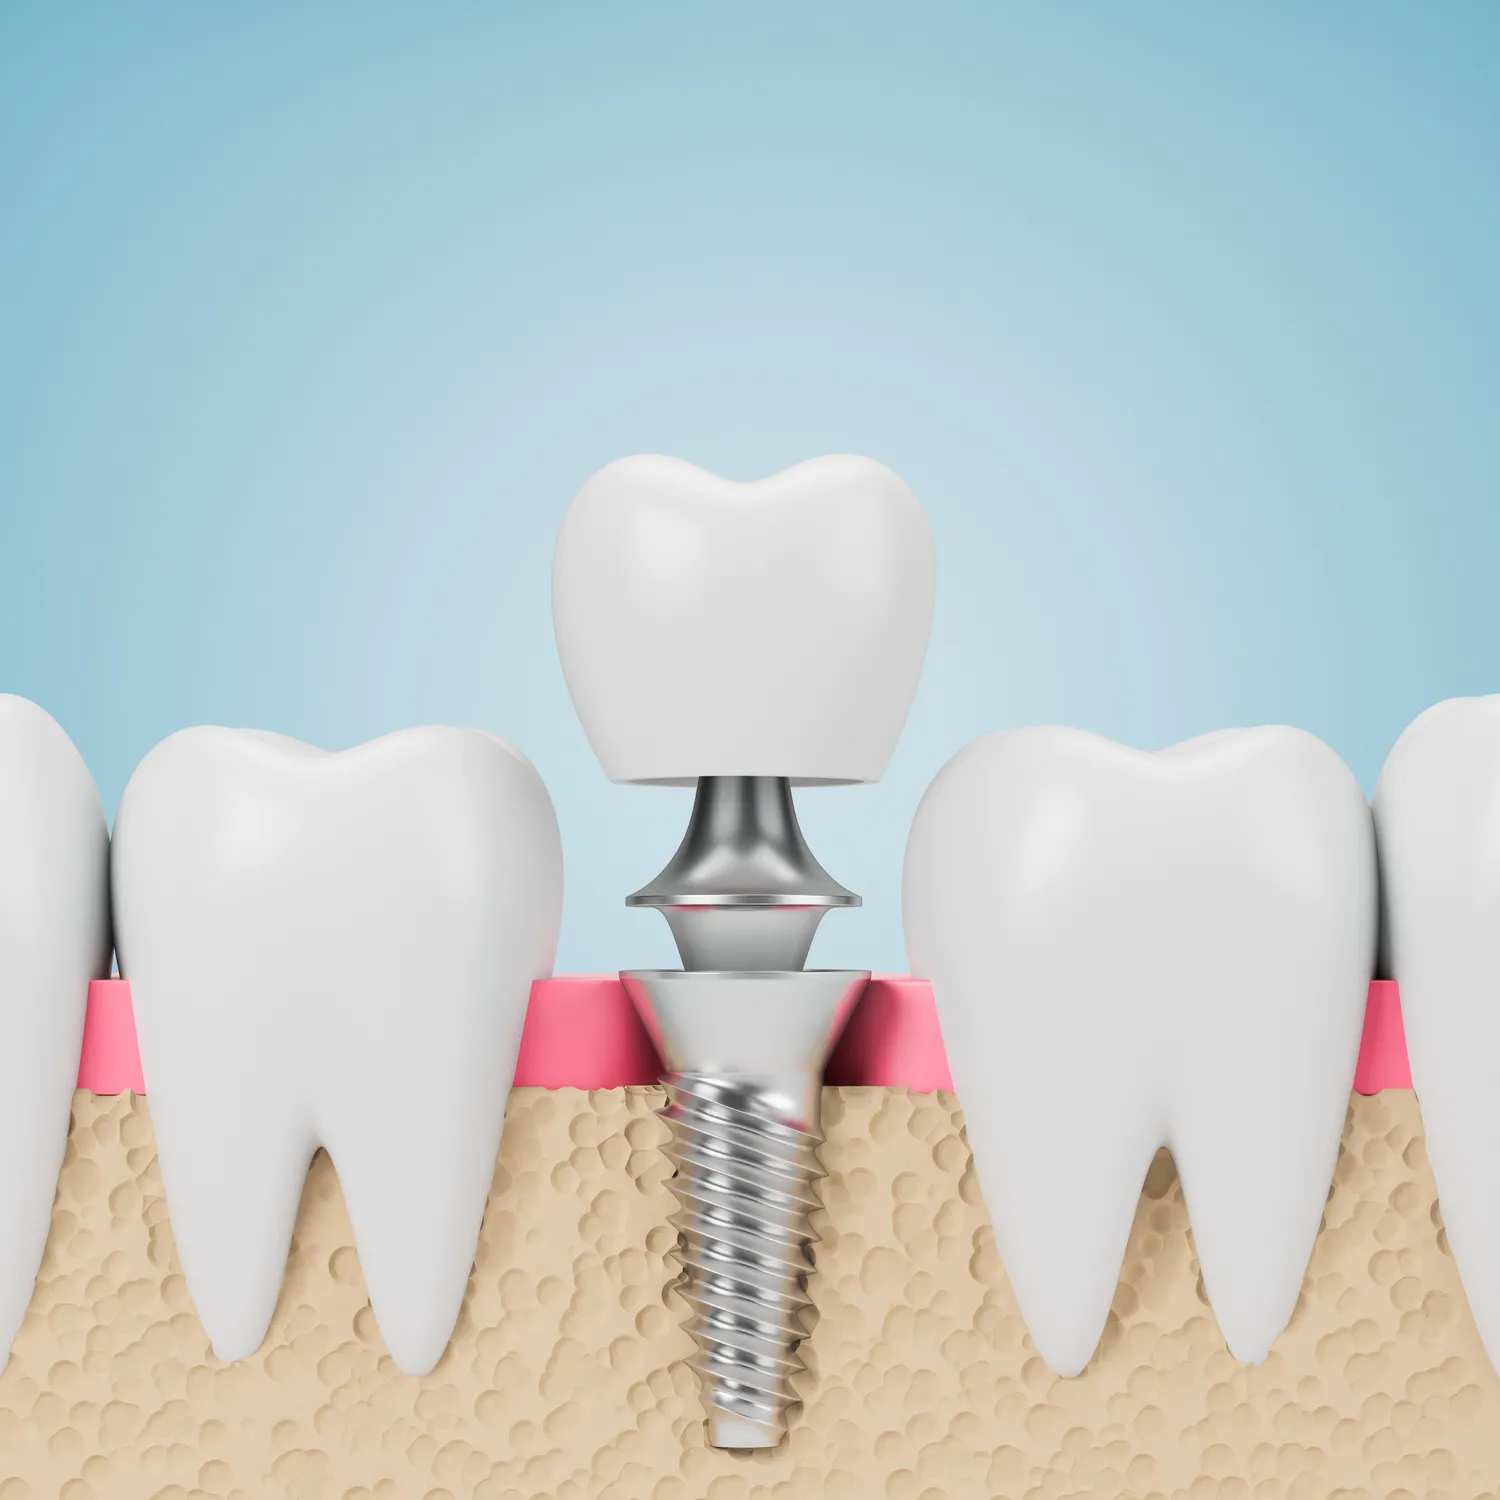

Implanty zębów na całą szczękę to rozwiązanie, które zyskuje coraz większą popularność w Lublinie. Dzięki nim pacjenci mogą cieszyć się pełnym uśmiechem oraz poprawić jakość życia. Jedną z głównych korzyści jest ich trwałość. Implanty wykonane są z materiałów biokompatybilnych, co oznacza, że dobrze integrują się z kością szczęki. W przeciwieństwie do tradycyjnych protez, które mogą powodować dyskomfort i ograniczenia w jedzeniu, implanty pozwalają na normalne funkcjonowanie. Kolejnym atutem jest estetyka. Implanty wyglądają jak naturalne zęby, co znacząco podnosi pewność siebie pacjentów. Dodatkowo, implanty pomagają w zachowaniu struktury kości szczęki, co jest istotne dla zachowania prawidłowej rysy twarzy.

Zakup implantów zębów na całą szczękę w Lublinie to proces, który wymaga staranności i odpowiedniego planowania. Pierwszym krokiem jest konsultacja ze specjalistą, który oceni stan zdrowia jamy ustnej pacjenta oraz zdecyduje o możliwości wszczepienia implantów. W trakcie wizyty lekarz może wykonać zdjęcia rentgenowskie lub tomografię komputerową, aby dokładnie zobaczyć strukturę kości i zaplanować zabieg. Po pozytywnej ocenie następuje etap przygotowawczy, który może obejmować leczenie chorób przyzębia lub ekstrakcję uszkodzonych zębów. Następnie przechodzi się do właściwego zabiegu wszczepienia implantów. Cały proces może trwać od kilku tygodni do kilku miesięcy, ponieważ konieczne jest zagojenie się tkanek wokół implantu przed umieszczeniem korony protetycznej.

Implanty zębów na całą szczękę różnią się od tradycyjnych protez w wielu aspektach, co sprawia, że są one coraz częściej wybieranym rozwiązaniem przez pacjentów w Lublinie. Przede wszystkim, implanty są trwale osadzone w kości szczęki, co zapewnia większą stabilność i komfort użytkowania. W przeciwieństwie do protez, które mogą przesuwać się podczas jedzenia czy mówienia, implanty pozwalają na normalne funkcjonowanie bez obaw o ich wypadnięcie. Kolejną istotną różnicą jest estetyka – implanty wyglądają jak naturalne zęby i nie wymagają stosowania klejów ani innych środków mocujących. Ponadto, implanty pomagają w zachowaniu struktury kości szczęki, co jest kluczowe dla utrzymania prawidłowej rysy twarzy. Tradycyjne protezy mogą prowadzić do zaniku kości z powodu braku stymulacji, co z czasem może wpłynąć na wygląd twarzy pacjenta.

Nowoczesne technologie stosowane przy wszczepianiu implantów zębów na całą szczękę w Lublinie znacząco poprawiają jakość i efektywność tego typu zabiegów. Jedną z najważniejszych innowacji jest wykorzystanie tomografii komputerowej do dokładnego obrazowania struktury kości przed przystąpieniem do zabiegu. Dzięki temu lekarze mogą precyzyjnie zaplanować lokalizację implantu oraz ocenić warunki anatomiczne pacjenta. Kolejną nowością są systemy cyfrowego projektowania uśmiechu (CAD/CAM), które umożliwiają stworzenie spersonalizowanych koron protetycznych idealnie dopasowanych do kształtu i koloru naturalnych zębów pacjenta. Technologia ta pozwala na szybsze wykonanie prac protetycznych oraz zwiększa ich estetykę. Dodatkowo, niektóre kliniki oferują możliwość zastosowania tzw. „implantacji natychmiastowej”, gdzie implanty są wszczepiane bezpośrednio po ekstrakcji zębów, co skraca czas leczenia i minimalizuje dyskomfort dla pacjenta.